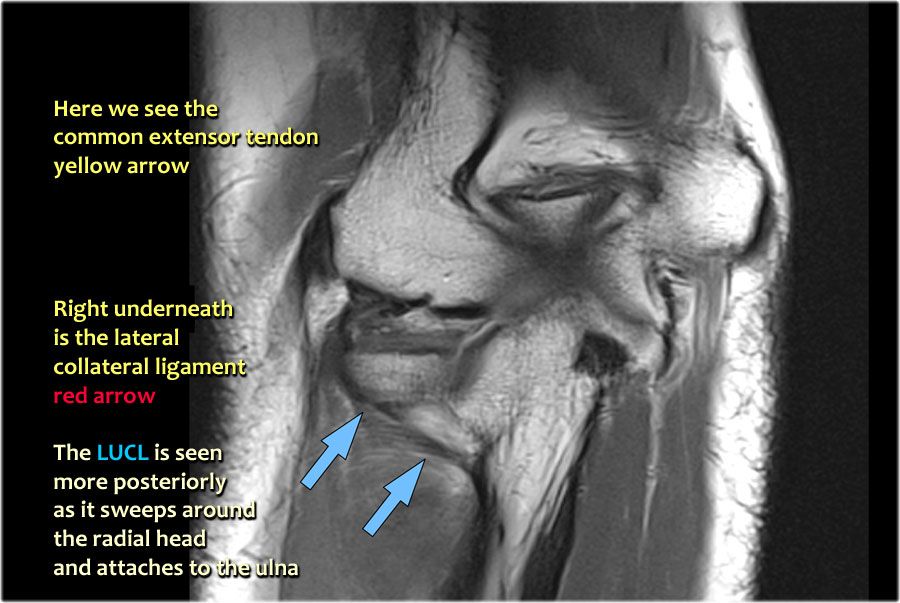

Common extensor tendon

Originates at the lateral epicondyle.

Dây chằng bên ngoài

Xuất phát ngay bên dưới điểm bám của gân duỗi chung.

Dây chằng bên trụ ngoài

Đây là một thuật ngữ có phần khó hiểu dùng để chỉ một gân cũng xuất phát ngay bên dưới gân duỗi chung. Nó vòng xuống phía sau chỏm quay và bám vào vùng xương trụ được gọi là mào cơ ngửa – xem hình ảnh mặt bên.

Khi bạn tìm kiếm dây chằng bên quay, trước tiên hãy cố gắng xác định gân duỗi chung, vì ngay bên dưới nó bạn sẽ tìm thấy dây chằng bên quay (mũi tên vàng).

Khi bạn di chuyển về phía sau hơn, bạn sẽ thấy LUCL – dây chằng bên trụ ngoài, quét ra phía sau chỏm quay (mũi tên trắng).

Dây chằng vòng thường khó phân biệt với dây chằng bên quay (RCL), nhưng đôi khi có thể được xác định trên phim chụp MR-arthrogram theo mặt phẳng đứng dọc.